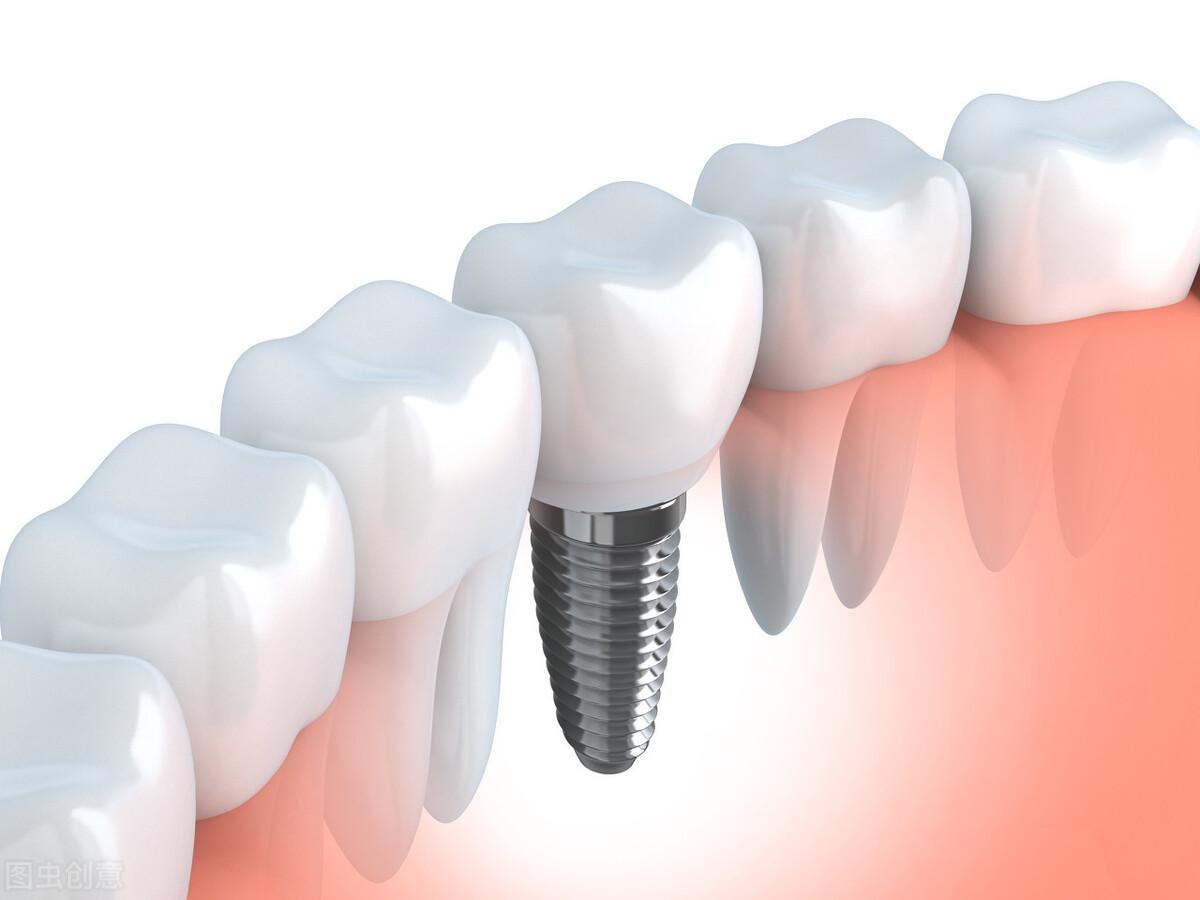

種植牙,全稱為人工種植牙,分成三個部分:種植體(人工牙根)、基臺(連接體)和牙冠(牙齒)。

種植體是一種高度精密的螺絲構(gòu)造,它外部的螺紋和微表面結(jié)構(gòu)與牙床骨接觸,引導(dǎo)牙床骨細(xì)胞生長到種植體表面,以達(dá)到種植體與牙床骨充分結(jié)合,增強(qiáng)其咀嚼力量及穩(wěn)定性能的目的。